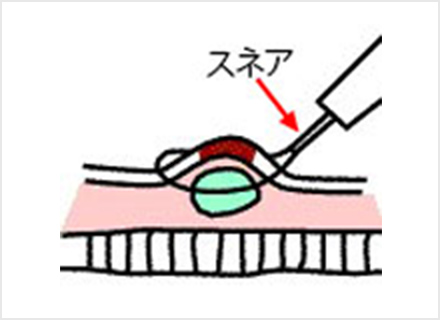

内視鏡的粘膜切除術:EMR(Endoscopic mucosal resection)

スネアと呼ばれる金属の輪を病変部に引っ掛け、高周波電流を流して病変を切り取ります。EMRは、治療が比較的短時間ですみますが、一度に切り取ることができる病変の大きさは、スネアの大きさ(約2cm)までと制限があります。